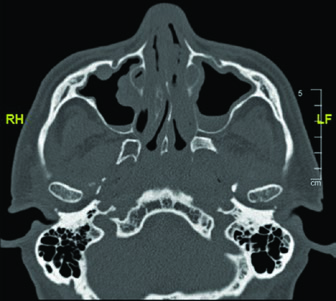

Bone involvement requires specific assessment using bone windows on CT. The image shows periosteal reaction at the posterior aspect of the left mandibular ramus, suggesting direct involvement. When confirmed, the bony structure must be incorporated into the CTV with appropriate margin.

These findings highlight the importance of a thorough imaging study before simulation. The combination of soft tissue and bone windows on the same CT ensures that no tumor extension goes undetected.

When bone involvement is detected, the extent of mandibular irradiation must be carefully balanced against the risk of osteoradionecrosis (ORN). Including the involved bone segment with adequate margin is essential for local control, but extending CTV coverage unnecessarily into healthy mandibular bone increases ORN risk without oncologic benefit. The use of dose painting — delivering higher doses to the involved segment while limiting dose to uninvolved bone — can help achieve this balance when IMRT or VMAT techniques are available.